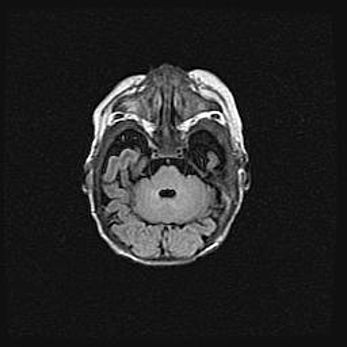

Неполная лизэнцефалия (пахигирия). Открытая гидроцефалия.

Возраст: 17 дней

Вес: 3110 г

Пол: мужской

Окружность головы: 33,5 см

Срок гестации: 35-36 недель

Лизэнцефалия—недоразвитие корковой пластинки и мозговых извилин в результате нарушения миграции нейронов коры. Поверхность мозговых полушарий гладкая. Микроскопически выявляется отсутствие нормальных слоев коры и скопление групп нейронов в подкорковом белом веществе.

Пахигирия—уменьшение числа вторичных извилин. В пораженном полушарии нервные клетки образуют толстый недифференцированный слой с неправильно расположенными нервными волокнами и группами гетеротопных клеток. Нервные клетки незрелые. Белое вещество истончено. При этом нередко аномально развит корково-спинномозговой путь.